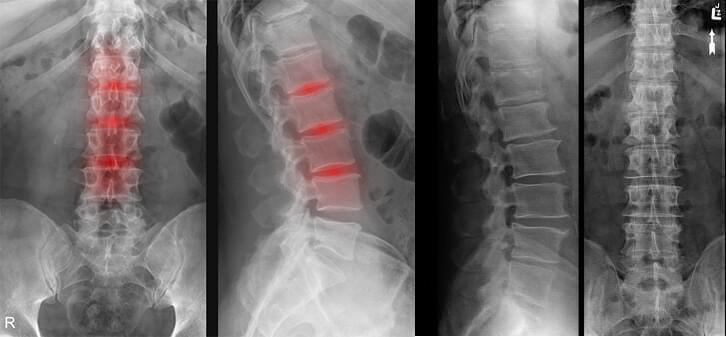

53 éves vagyok, szerintem még korai az idős korról beszélni ebben az életszakaszban, mégis osteochondrosisszal diagnosztizáltak a kórházban, intravénás kezelést kaptam és injekciókat, majd felírták a gyógyszereket és otthon kellett folytatnom a kezelést, sok tornázás mellett. Sajnos, ennek a kezelésnek nem sok hatása volt.

A gerincem olyan módon elhajlott, hogy mindig nagyon fájt kiegyenesíteni. Szégyelltem magam a menyem előtt, hogy neki kellett a konyhában dolgoznia és főznie helyettem. Nagyon kellemetlen volt, azért az 50 év mégsem 80. Az unokáimra is szerettem volna vigyázni, de fel sem bírtam emelni őket.